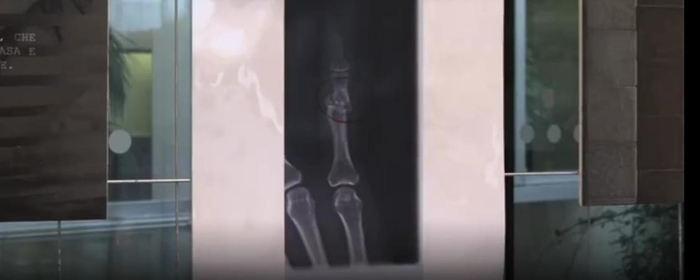

各国也都对家暴加强重视,进行反家暴教育。11月22日,意大利一家医院展出了遭受家暴女性的X光片,她想展示自己26年行医岁月所见到的残酷事实,把女性真实受到的伤害展现出来。罗马前几日也有数万人游行抗议家暴,在抵达终点的时候,她们集体坐在地上为因家暴丧生的女性默哀。2018年,意大利共有119位女性死于家庭暴力,相当于每三天就有一名女性死于家暴。

意大利米兰一家医院展出的遭受家暴女性的X光片意大利米兰一家医院展出的遭受家暴女性的X光片